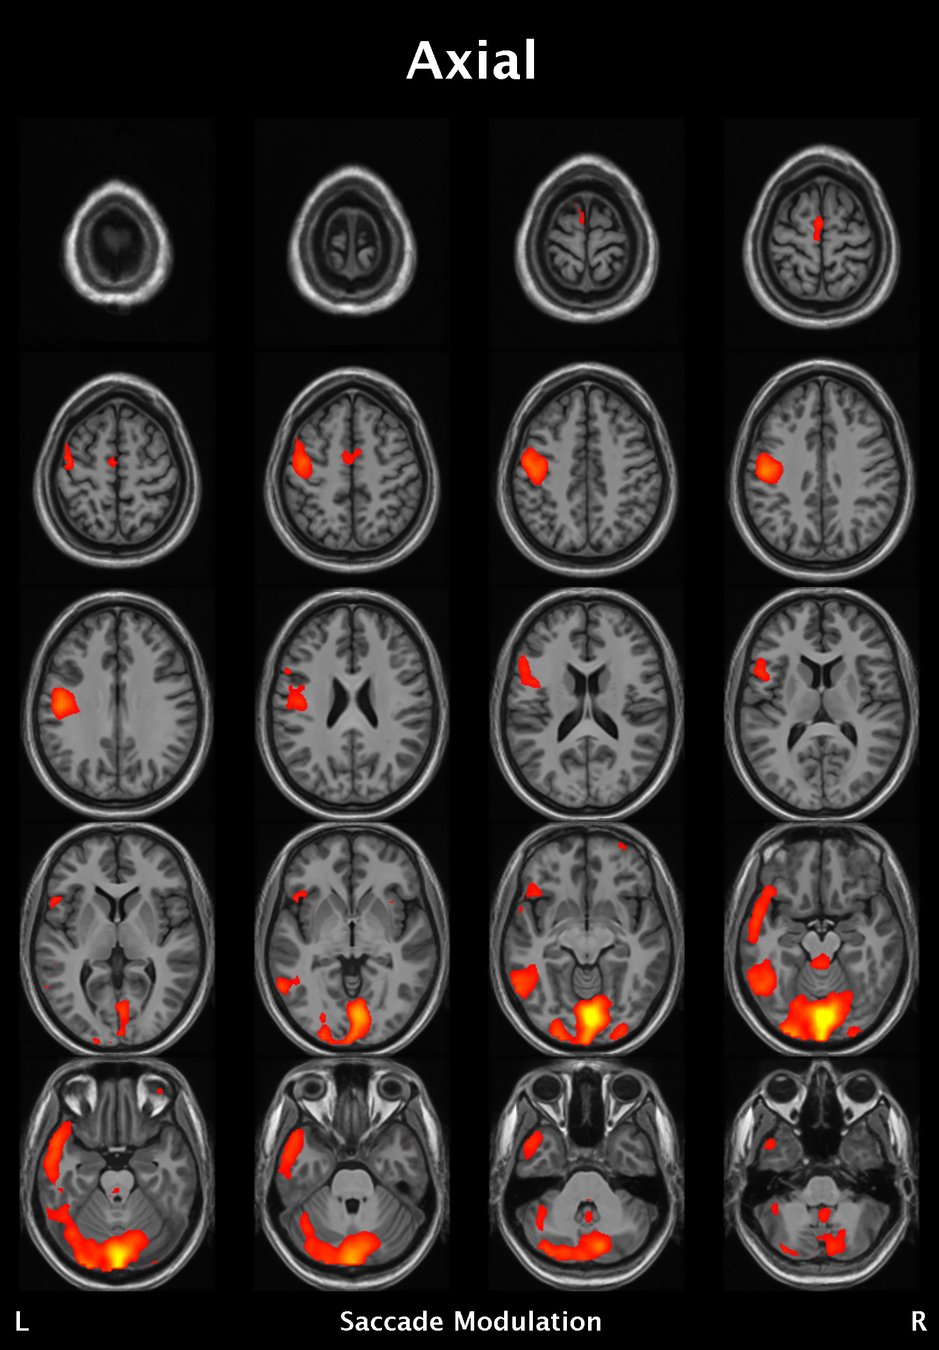

Results

Significant ROIs

Voxels Peak - x Peak - y Peak - z Anatomical location

1923 -1.5 79.5 -9 R/L Lingual Gyrus

495 52.5 -10.5 -18.0 L. Mid. Temporal Gyrus

395 46.5 16.5 33.0 L. Precentral Gyrus

135 1.5 38.5 -12.0 L. Ant. Cerebellum

56 7.5 19.5 -3.0 L. Thalamus

55 -22.5 -94.5 -9.0 R. Inf. Occipital Gyrus

55 52.5 -7.5 15.0 L. Inf. Frontal Gyrus

54 4.5 7.5 60.0 L. Medial Frontal Gyrus

29 -46.5 -7.5 -24.0 R. Temporal Pole